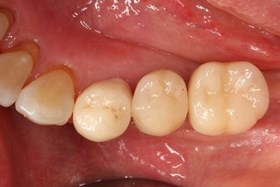

植牙後癒合狀況良好

因植牙恢復正常咬合